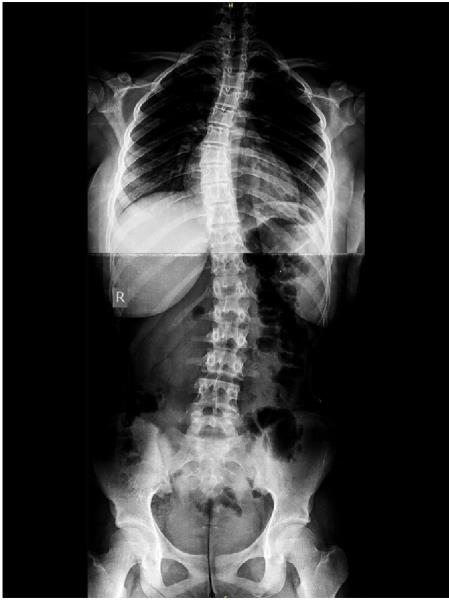

This case report introduces a threeyear integrative protocol that combines low-level laser therapy (L3T), targeted spinal manipulation, and therapeutic exercise to address AIS as a dynamic, frequency-sensitive condition. The results? A reduction in thoracic Cobb angle from 65 degrees to 24 degrees, lumbar from 36 degrees to 11 degrees, and sustained improvements in posture, pain, and mobility.

• Cobb angle reduction: 65 degrees to 24 degrees thoracic; 36 degrees to 11 degrees lumbar

The patient remained active in sports and academics, reporting improved confidence, mobility, and overall well-being. Follow-up radiographs confirmed structural improvements, while clinical assessments validated functional gains.